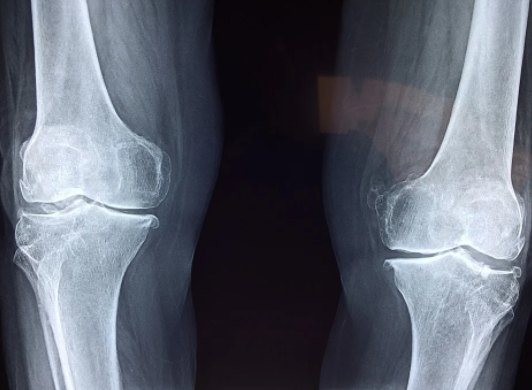

사람은 35세부터 골량이 서서히 줄다가 50세 전후로 매우 빠른 속도로 골량이 줄어든다고 한다.

이렇게 뼈의 양이 줄어들고 뼈가 얇아지면서 약해지게 되는 증상을 골다공증이라고 한다.

뼈가 약해지는 원인은 운동부족과 영양소결핍 등 다양한 원인이 있어 적당한 운동과 식습관이 매우 중요하다.